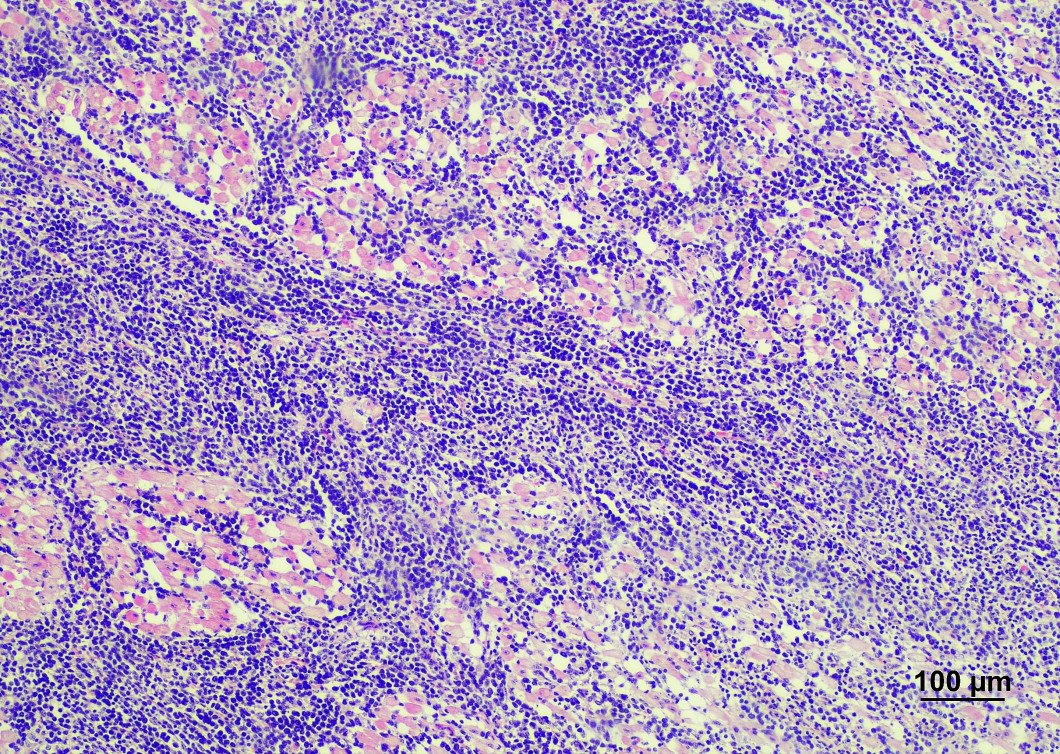

病理組織学的検査

血液や臓器の細胞や組織を顕微鏡で観察し、疾病の診断を行います。

牛伝染性リンパ腫 心臓の白色腫瘤のヘマトキシリン・エオジン染色(心筋に異型リンパ球が浸潤)